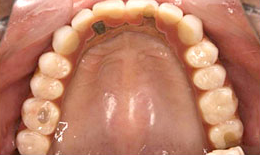

治療後

上顎

保存困難な歯を抜歯後、インプラントを7本埋め込み、ボーンアンカードブリッジを装着した